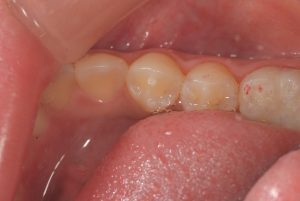

たとえばこちら

歯の中心に突起があるのがわかるでしょうか?

よく見てみると、ツノのようなものが生えているような状態があります。

これは中心結節(ちゅうしんけっせつ)とよばれ、下の歯の真ん中の歯(小臼歯)では出現率は1~4%ともいわれています。

上で上げている写真のお子さんも、実は中心結節が折れていましたが、レントゲン写真より神経は中になく症状もなかったので一安心でした。